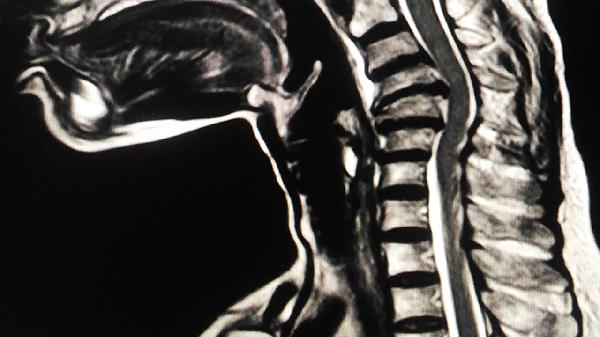

腰椎间盘向右侧突出可能压迫神经根,引起腰部放射性隐痛伴下肢麻木。急性期需卧床休息,配合腰椎牵引治疗,可遵医嘱使用甲钴胺片、依托考昔片或氟比洛芬凝胶贴膏,严重者需考虑椎间孔镜手术。

建议避免提重物或突然扭转腰部,睡眠时选择硬板床减轻腰椎压力。每日进行小燕飞或五点支撑等腰部锻炼,注意保暖防止受凉。若疼痛持续超过3天不缓解,或出现发热、血尿、下肢无力等症状,应及时至骨科或泌尿外科就诊完善CT或核磁共振检查。饮食上适量增加牛奶、豆制品等含钙食物,控制高嘌呤饮食预防结石形成。